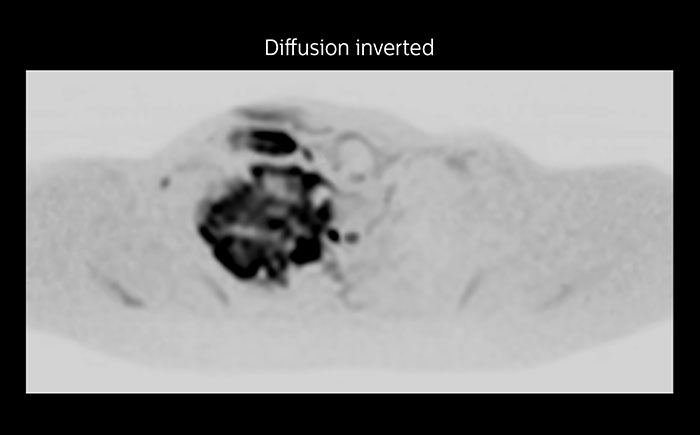

Although the area between the neck and the top of the lung is one of the most difficult areas for MRI, Prodiva 1.5T images show good quality in this 56-year-old male with Pancoast tumor on the right. mDIXON TFE images shows excellent fat suppression in the neck area and the DWI shows almost no distortion.